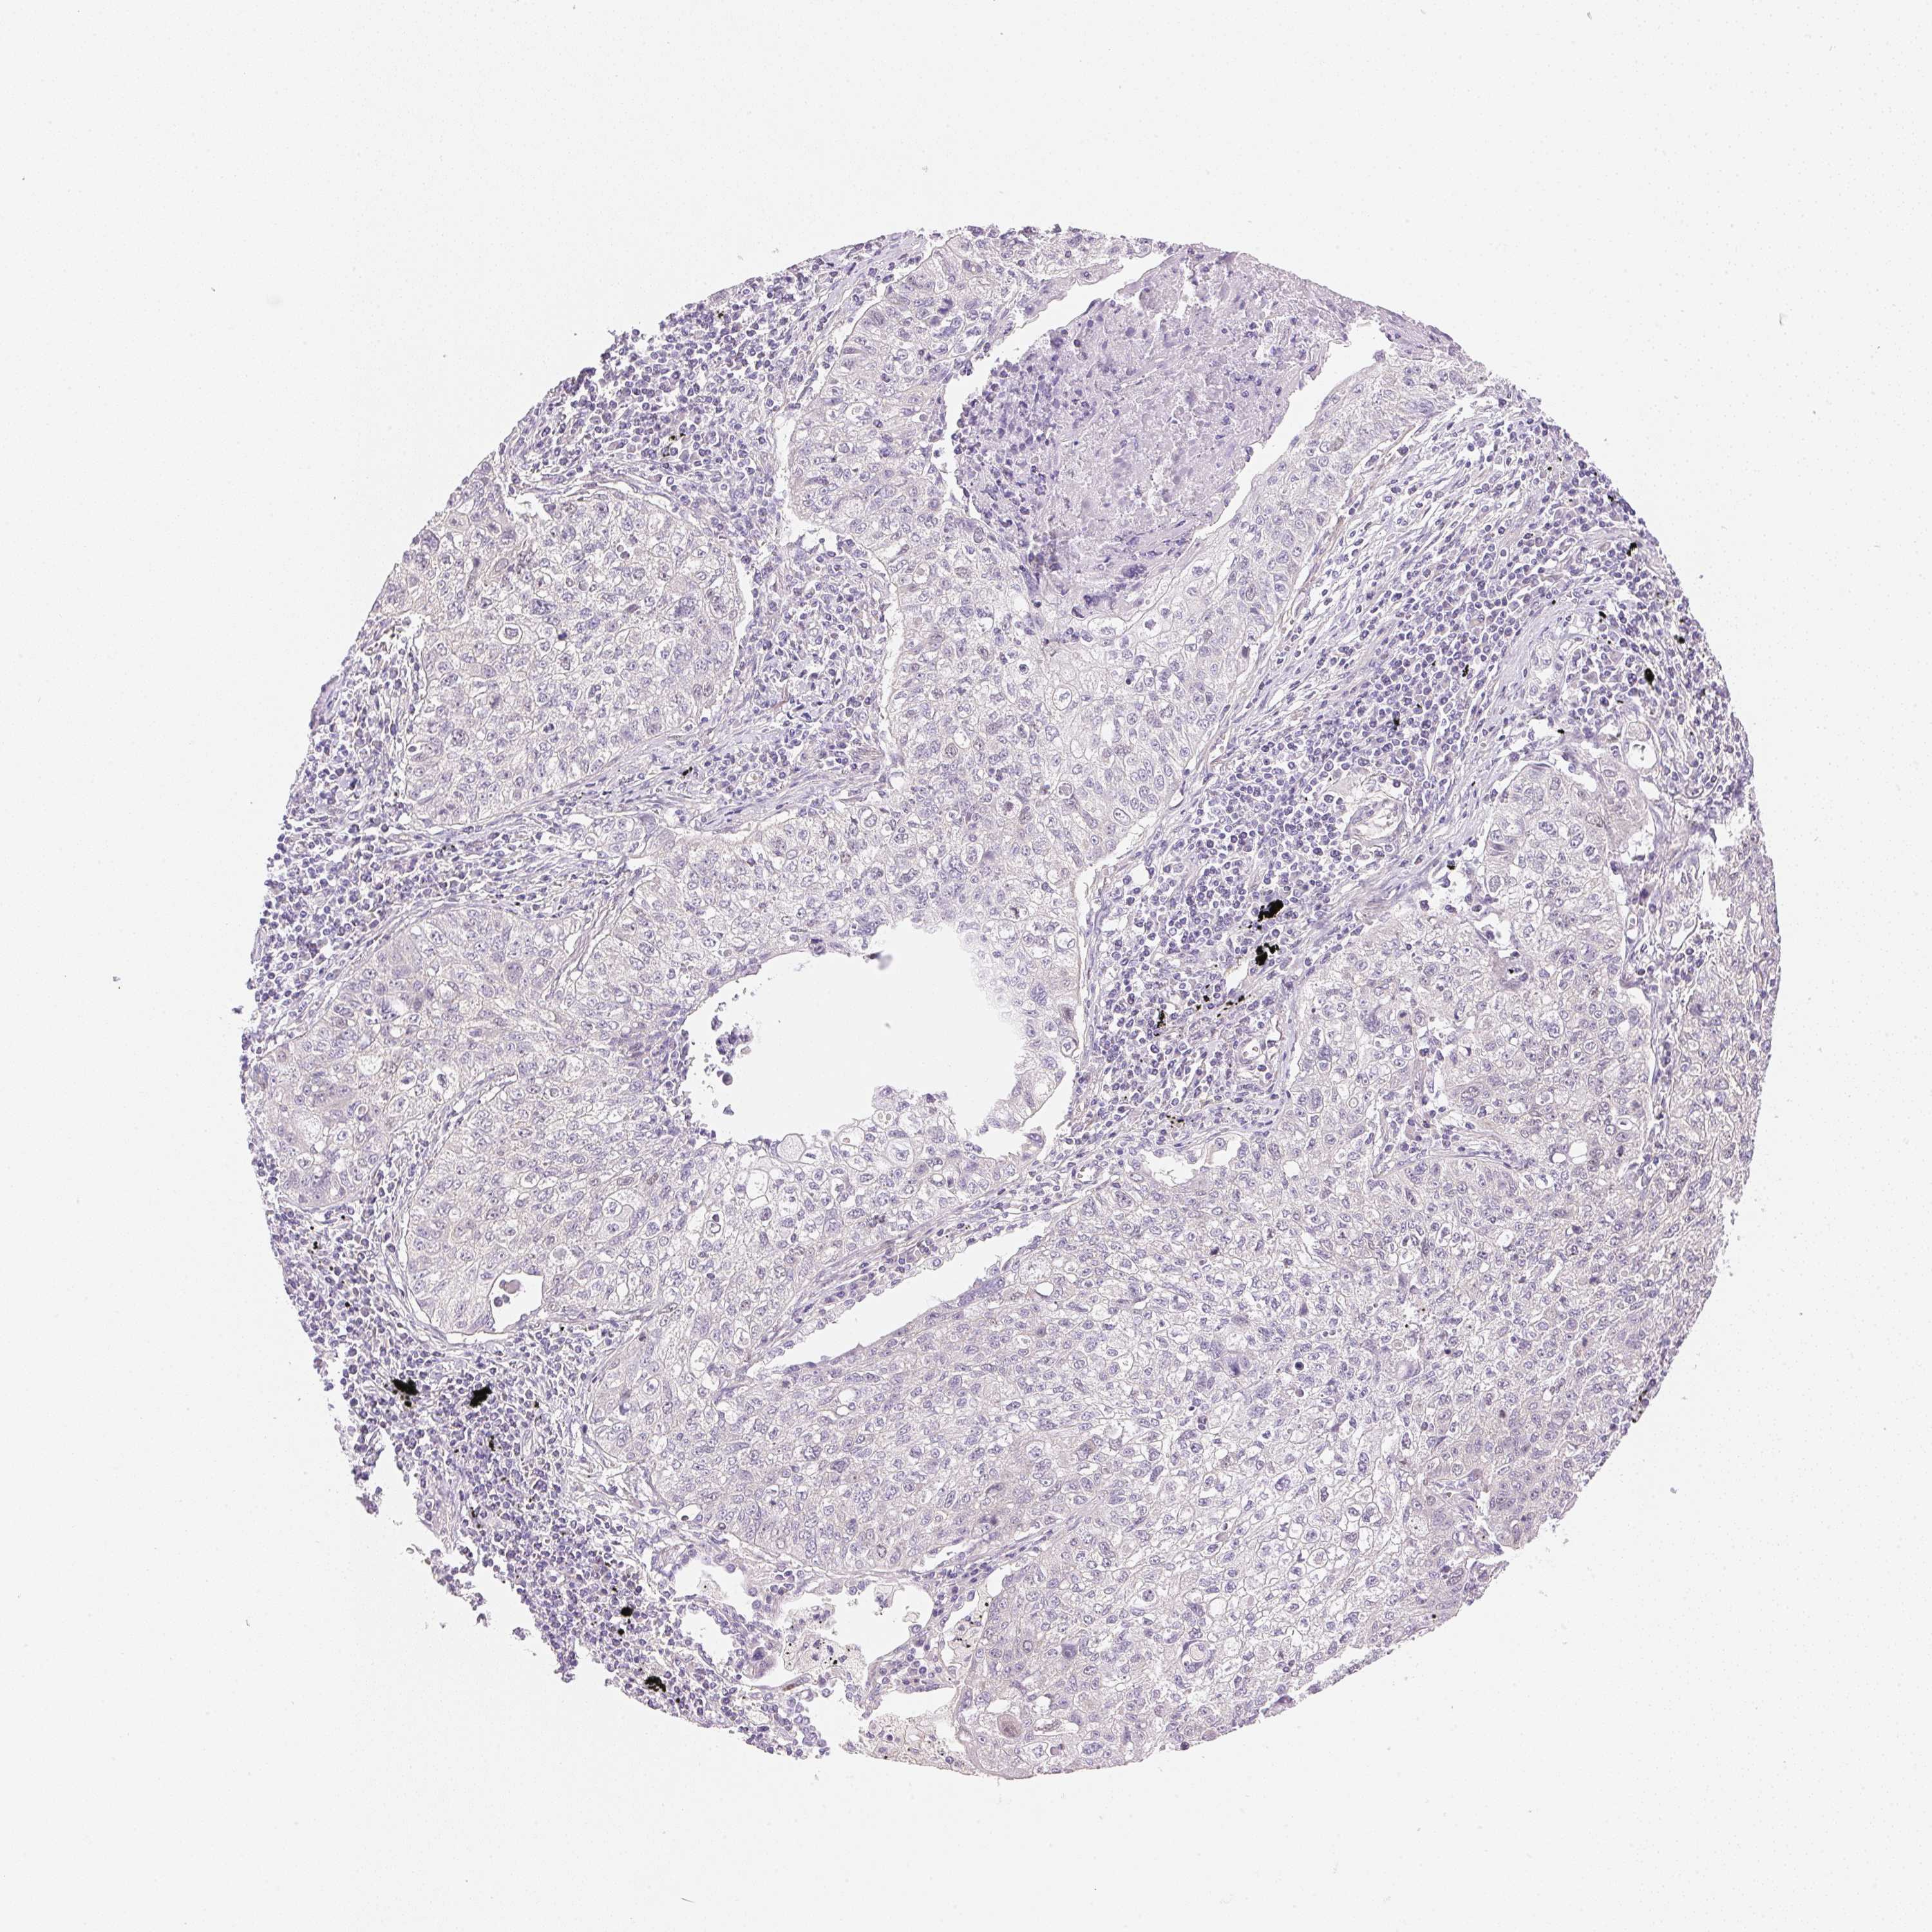

LUNG SQUAMOUS CELL CARCINOMA (TCGA) - Interactive survival scatter ploti

The Survival Scatter plot shows the clinical status (i.e. dead or alive) for all individuals in the patient cohort, based on the same data that underlies the corresponding Kaplan-Meier plots. Patients that are alive at last time for follow-up are shown in blue and patients who have died during the study are shown in red.

The x-axis shows the expression levels (FPKM) of the investigated gene in the tumor tissue at the time of diagnosis. The y-axis shows the follow-up time after diagnosis (years). Both axes are complimented with kernel density curves demonstrating the data density over the axes. The top density plot shows the expression levels (FPKM) distribution among dead (red) and alive patients (blue). The right density plot shows the data density of the survived years of dead patients with high and low expression levels respectively, stratified using the cutoff indicated by the vertical dashed line through the Survival Scatter plot. This cutoff is automatically defined based on the FPKM cutoff that minimizes the p-score. The cutoff can be changed by dragging the vertical line or by entering a cutoff value in the square labeled "Current cut-off".

Under the Survival Scatter plot the p-score landscape (black curve; left axis) is shown together with dead median separation (red curve; right axis). Dead median separation is the difference in median mRNA expression between patients who have died with high and low expression, respectively. It is calculated as follows: median FPKM expression of dead patients with high expression - median FPKM expression of dead patients with low expression. This is intended to aid the user in visually exploring custom cutoffs and the associated p-scores and dead median separation.

Individual patient data is displayed and can be filtered by clicking on one or more of the category buttons on the top of the page. Categories describing expression level and patient information include: high, low, alive, dead, female, male and tumor stages. The scale of the x-axis can be toggled between linear and log-scale by clicking on the "x log" button. Mouse-over function shows TCGA ID, patient information and mRNA expression (FPKM) for each patient.

& Survival analysisi

Kaplan-Meier plots summarize results from analysis of correlation between mRNA expression level and patient survival. Patients were divided based on level of expression into one of the two groups "low" (under cut off) or "high" (over cut off). X-axis shows time for survival (years) and y-axis shows the probability of survival, where 1.0 corresponds to 100 percent.

SMTN is not prognostic in Lung Squamous Cell Carcinoma (TCGA)

: 21.26